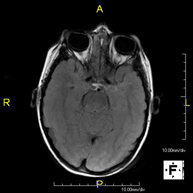

- Brain MRI (cranial)

This non-invasive diagnostic procedure uses an electromagnetic field and radio waves (from a transmitter and receiver) to acquire high-definition anatomical images of the brain. It is a radiation-free procedure. Indicated for: vascular problems, memory loss, epilepsy, headache, malformations, suspected tumour, meningitis.